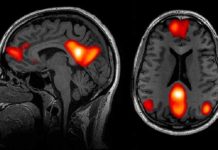

Vagusni živac- nije samo električna žica između mozga i utrobe, već pravi tajni most...

Postoji živac koji malo tko zaista poznaje, ali koji tiho upravlja orkestrom našeg tijela.

To je...